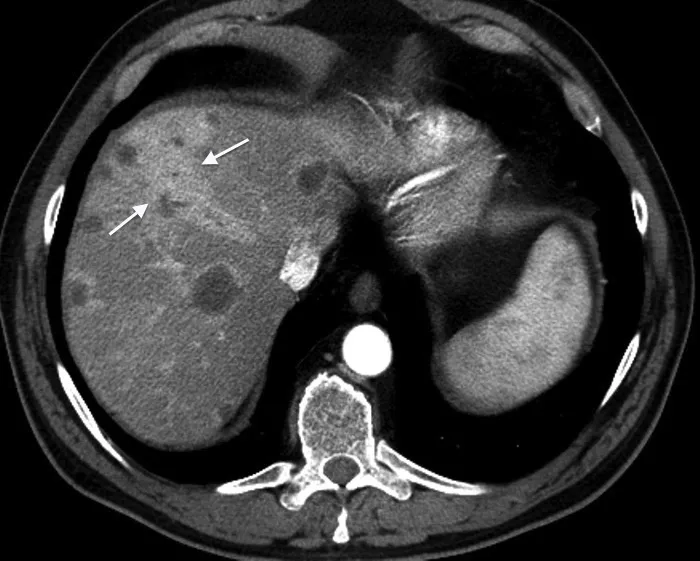

An ultrasound scan showing signs of pseudoappendicitis